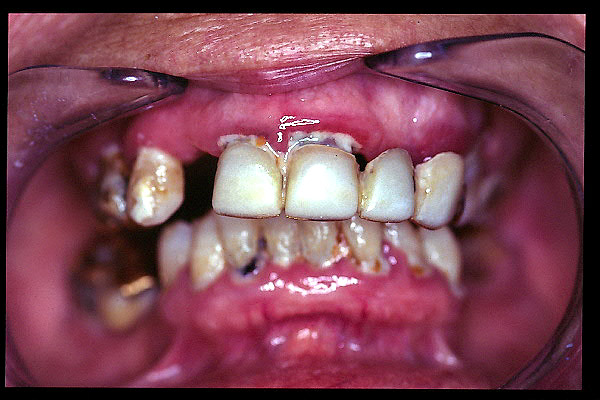

CM Enfermedad periodontal avanzada con caries. Mala higiene.